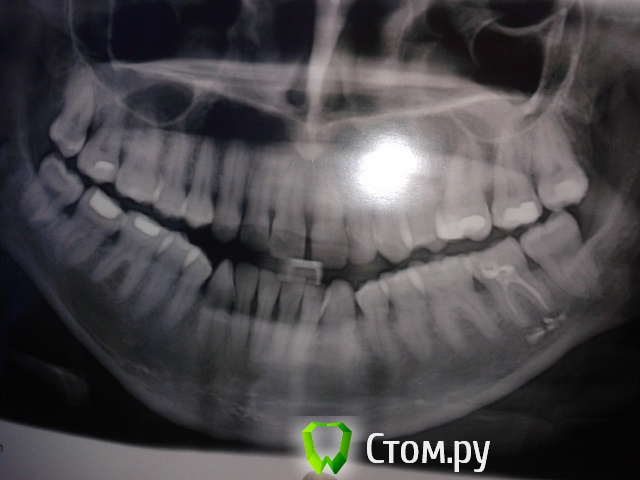

stasya147 Опубликовано 10 октября, 2014 Поделиться Опубликовано 10 октября, 2014 (изменено) В подростковом возрасте вверху слева удалили зуб,которому не хватало места(полез когда уже все выросли). Из-за этого случился перекос центра, ла еще мезиальный прикус дал о себе знать. Зубы разъехались как могли. Теперь как решить эту проблему не знаю! Была у 3-х ортов.1-й говорит надо удалать 2 4-ки снизу, 1 сверху.2-ая сказала, что только операция на нижнюю челюсть.3-й сказал, что операция не нужна, я бы удалил одну 4-ку слева снизу.Какой лучше вариант? Операцию отсекаю сразу. Спасибо.http://s009.radikal.ru/i307/1410/33/50ee08438645.jpghttp://s019.radikal.ru/i641/1410/95/b1705f8fbd6b.jpg Изменено 10 октября, 2014 пользователем stasya147 Ссылка на комментарий

Ayrat_zub Опубликовано 12 октября, 2014 Поделиться Опубликовано 12 октября, 2014 оптг полностью сфотографируйте, а не только участок где зубы) и под прямым углом, чтобы искажений не было. Ссылка на комментарий

Ayrat_zub Опубликовано 12 октября, 2014 Поделиться Опубликовано 12 октября, 2014 (изменено) ещебы ТРГ получить, а в идеале и КТ, но 3-й вариант точно отпадает)1-й с большими оговорками, еще как-то возможен, еще 4-й есть) раскрытие промежутка под удаленный ранее зуб, но нужно больше информации по вашему случаю Изменено 12 октября, 2014 пользователем Ayrat_zub Ссылка на комментарий